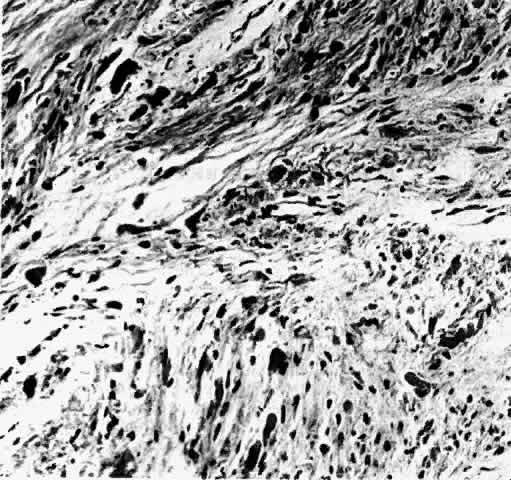

may be extension to posterior structures.4 Most optic gliomas are classified as juvenile pilocytic astrocytomas and

have a benign histologic appearance. Pilocytic refers to the spindle-shaped astrocytes with elongated nuclei that are

often arranged in a parallel fashion (Fig. 7). Oligodendroglial cells may be scattered throughout the glioma. These

tumors can contain carrot- or cigar-shaped eosinophilic astrocytic cytoplasmic

inclusions known as Rosenthal fibers4 (Fig. 8). Microcystoid extracellular spaces containing acid mucopolysaccharide

generated by mucin-producing astrocytes are often seen.85 Less common features can include capillary hyperplasia, mitotic figures, tissue

necrosis with hemorrhage,86 and glial giant cells.4